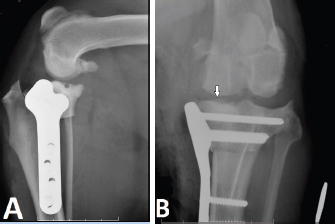

Preoperative radiographs were evaluated and the TPA was measured using a conventional method (Dismukes et al., 2008) by one observer (J.V.J.C.). Postoperative radiographs were evaluated for the location of placement of the proximal jig pins based on the location and trajectory of the radiographically evident pin tract. The shortest distance from the proximal jig pin hole to the osteochondral junction of the tibial plateau on the mediolateral projection radiographs was measured. The pin hole tract was also reviewed on the caudocranial views. Pin placement was considered intra-articular if the pin tract penetrated the osteochondral junction on either radiographic view. The erroneous placement was classified according to the location of the intra-articular jig pin placement as a medial or lateral plateau. Medial plateau intra-articular jig pin placement was defined as a visible radiolucent tract directly over and through the osteochondral junction of the medial tibial plateau in the mediolateral view (Fig. 1A and B). Lateral plateau intra-articular jig pin placement was defined as a radiolucent tract within 3 mm of the medial subchondral bone surface on the mediolateral view (Fig. 2A), and jig pin trajectory penetrating the osteochondral junction of the lateral tibial plateau on the caudocranial view (Fig. 2B). For those dogs that had evidence of intra-articular jig pin placement, details such as age, sex, breed, and weight were recorded.

Fig. 1. Mediolateral (A) and craniocaudal (B) radiographs illustrate medial tibial intra-articular jig pin hole placement. The white arrow indicates an osteochondral fragment created during intra-articular pin placement.